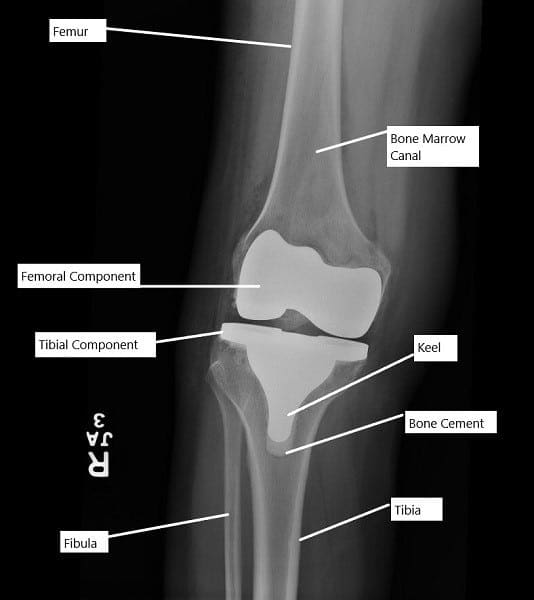

Radiografía que muestra un reemplazo total de rodilla.